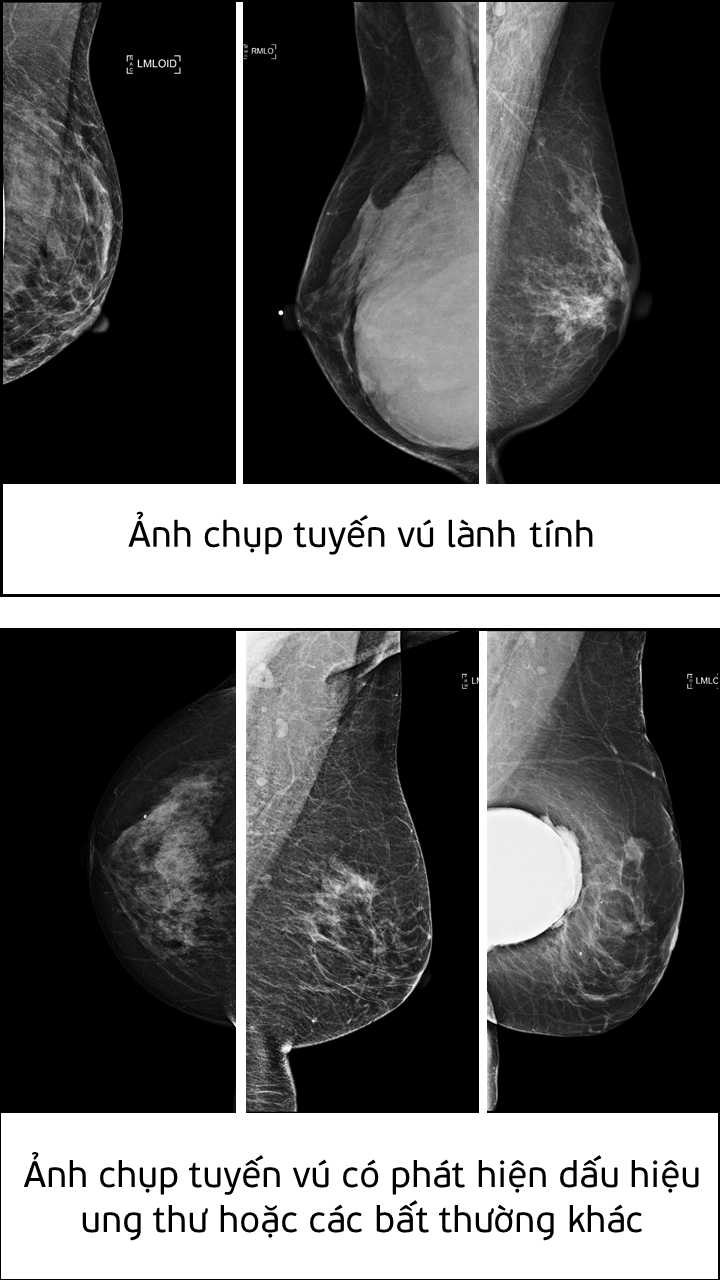

| Ảnh chụp tuyến vú lành tính và ảnh chụp tuyến vú có phát hiện dấu hiệu ung thư hoặc các bất thường khác |

Giải pháp AI do Nguyễn Hồng Đăng phát triển có thể tự động nhận diện các dấu hiệu bệnh ung thư tuyến vú từ một vùng rất nhỏ trong nhũ ảnh. Giải pháp này có thể tích hợp vào hệ thống hỗ trợ phân tích (Computer-aided diagnosis - CADx systems) nhằm cải thiện tính chính xác trong việc chẩn đoán và khám chữa bệnh.

Theo đánh giá của Ban giám khảo, giải pháp của Nguyễn Hồng Đăng đã giải quyết được tình trạng mất cân bằng dữ liệu trong huấn luyện mô hình AI. Trong tệp dữ liệu mà cuộc thi đưa ra, tỷ lệ mẫu ung thư ác tính được gán nhãn chỉ chiếm khoảng 2% tổng số lượng mẫu, trong khi số lượng mẫu còn lại được gán nhãn lành tính hoặc bình thường chiếm 98%. Tình trạng mất cân bằng dữ liệu này có thể khiến cho trí tuệ nhân tạo dự đoán sai.